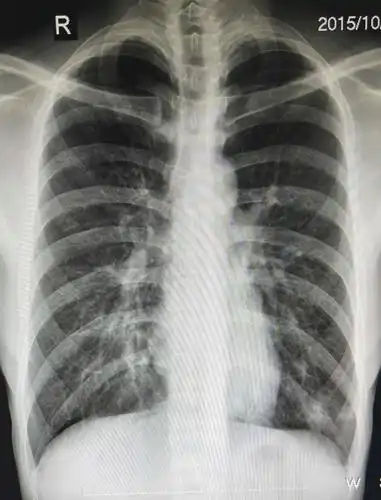

小孩四岁发烧不退诊断为肺炎,帮忙看下两次片子是否好了